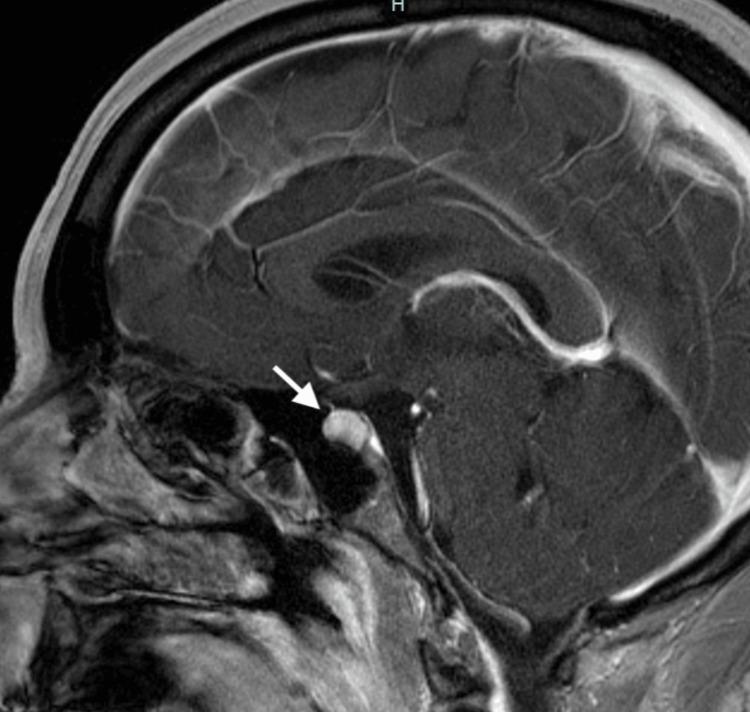

Autoimmune hypophysitis (AH) is an uncommon condition where there is inflammation of the pituitary gland which leads to hormonal imbalances. It is often associated with autoimmune diseases; however, a case is yet to be reported with an association of AH with seronegative rheumatoid arthritis (RA). We present a case of a 45-year-old female who complained of polyuria/polydipsia and rapid weight gain. An MRI of the head revealed enlargement of the pituitary gland, concerning for AH. Although she was initially treated for diabetes insipidus, she began reporting new complaints of joint pains and morning stiffness. She was clinically diagnosed with seronegative RA and improved with a trial of hydroxychloroquine. A repeat MRI showed improvement in the abnormal pituitary findings, and the patient was closely monitored with a multidisciplinary approach. Diagnosing and managing patients with AH are topics that are still being explored and researched as it is a relatively rare pathology. Consequently, we found the need to discuss the relationship of AH with seronegative RA and delve into the various diagnostic and treatment approaches.

自身免疫性垂体炎(AH)是一种罕见的疾病,其特征为垂体发生炎症,进而导致激素失衡。它常与自身免疫性疾病相关;然而,AH与血清阴性类风湿关节炎(RA)相关的病例尚未见报道。我们报告一例45岁女性患者,她主诉多尿/烦渴及体重快速增加。头部MRI显示垂体增大,怀疑为AH。尽管她最初接受了尿崩症的治疗,但她开始报告新的关节疼痛和晨僵症状。她临床诊断为血清阴性RA,试用羟氯喹后病情改善。复查MRI显示垂体异常表现有所改善,患者采用多学科方法进行密切监测。由于AH是一种相对罕见的病理情况,对AH患者的诊断和管理仍是正在探索和研究的课题。因此,我们认为有必要讨论AH与血清阴性RA的关系,并深入探讨各种诊断和治疗方法。